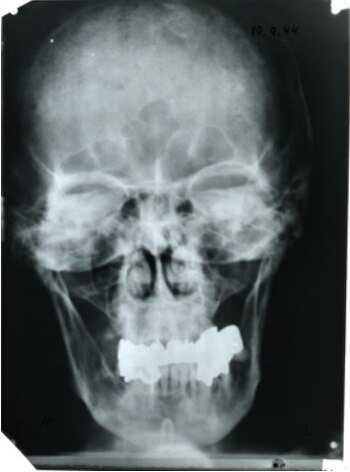

La morfología del fragmento correspondía con las radiografías del cráneo de Hitler tomadas antes de su muerte, estimó el estudio.

El equipo francés pudo analizar un fragmento del cráneo que fue atribuido al "Fuhrer", que tenía un agujero en el lado izquierdo que probablemente fue provocado por el impacto de la bala.

El análisis de la mala dentadura de Hitler y de varias piezas, no encontró ningún rastro de carne, ya que el dictador nazi era vegetariano, indicó Charlier.

El análisis de los dientes no encontró ningún rastro de pólvora, lo que indica que el revólver no entró en la boca y que más probablemente fue apuntado al cuello o a la frente.

Además, los depósitos azulados en sus piezas de dentadura postiza podrían indicar "que hubo una reacción entre el cianuro y la dentadura", dijo el investigador.